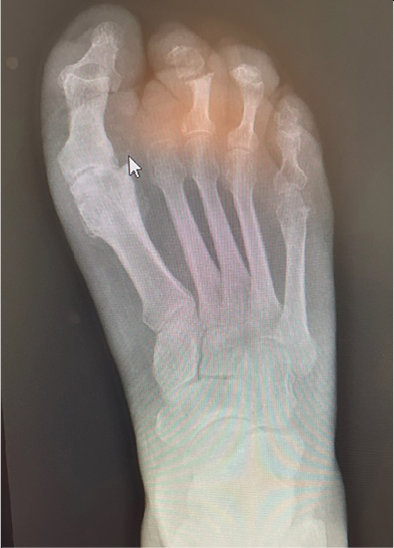

- X-rays indicating erosive changes of the distal phalanx of the third toe,

- MRI with and without contrast showing increased uptake on T-2 weighted images of the second toe of the right foot (see Figures 1 & 2),

In the preoperative planning, we considered performing a more curative procedure to address the patient’s condition. At the initial onset of this patient’s course, right after noninvasive Doppler studies, we referred the patient to the interventional radiology department. Prior to podiatric surgical intervention, interventional radiology performed a bland balloon angioplasty of the medial plantar artery to increase perfusion to the forefoot. This was confirmed by a repeat CTA (see Figure 5). Three weeks post-procedure there was an improvement in sensation of the forefoot. We amputated the second toe as well as a hammertoe repair of the third toe (see Figure 6). We also obtained intraoperative cultures. The patient had an injection of an advanced biologics-connective tissue matrix implant to support healing.